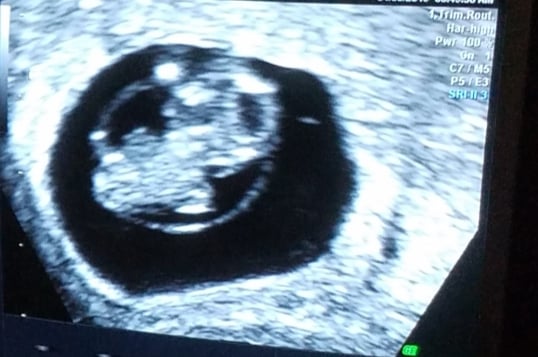

First u/s today at 6w4d. Honestly this early it’s just all blobs to me but my dr diligently showed us the flutter of the HB and also had us listen. I think HB was clocked at 138. Here’s the pic with sound waves. I think the print out said measuring 6w1d but my dr said the embryo was measuring at .4 cm and anything between .25 and .5 would be just right.

First u/s at 6+3. We weren’t told the exact HR, though everything is measuring on time.